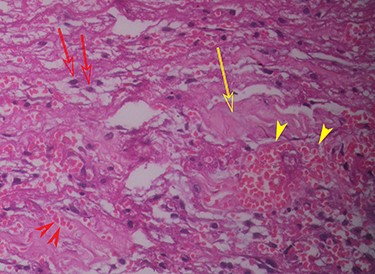

Histopathology (haematoxylin and eosin staining) of the cyst wall (higher magnification) shows haemorrhage (red arrowhead), vascularity (yellow arrowhead), mononuclear inflammatory cells (red arrow) and collagen (yellow arrow).